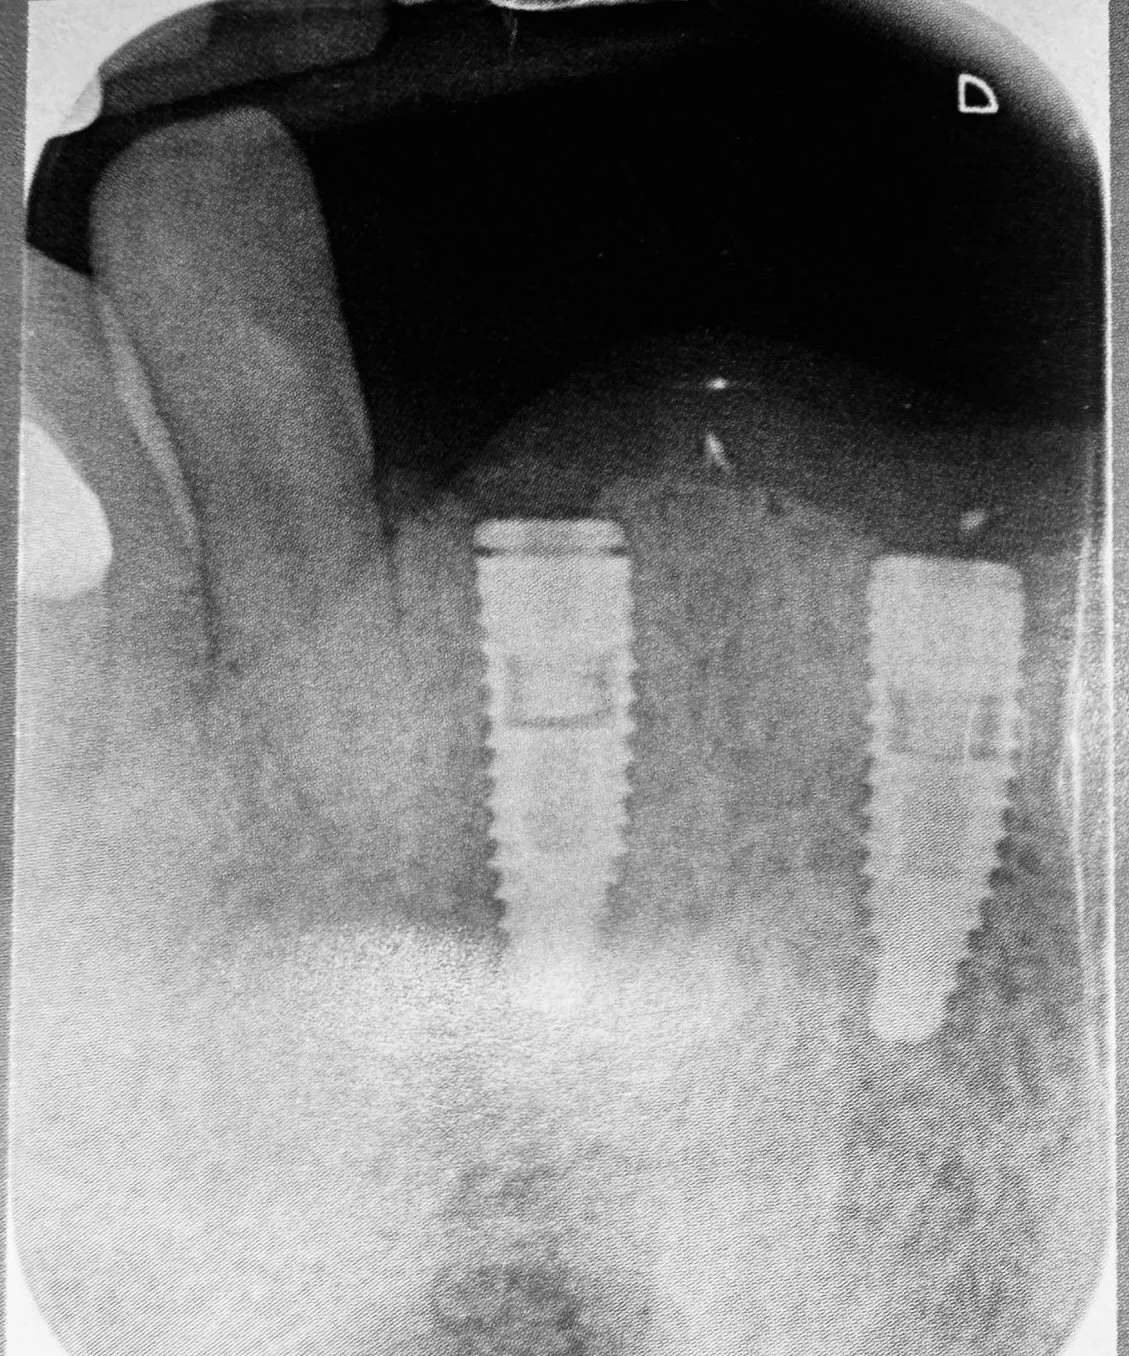

Estrazione, Rigenerazione Ossea e Riabilitazione Implantare

Riabilitazione post estrazione con impianto